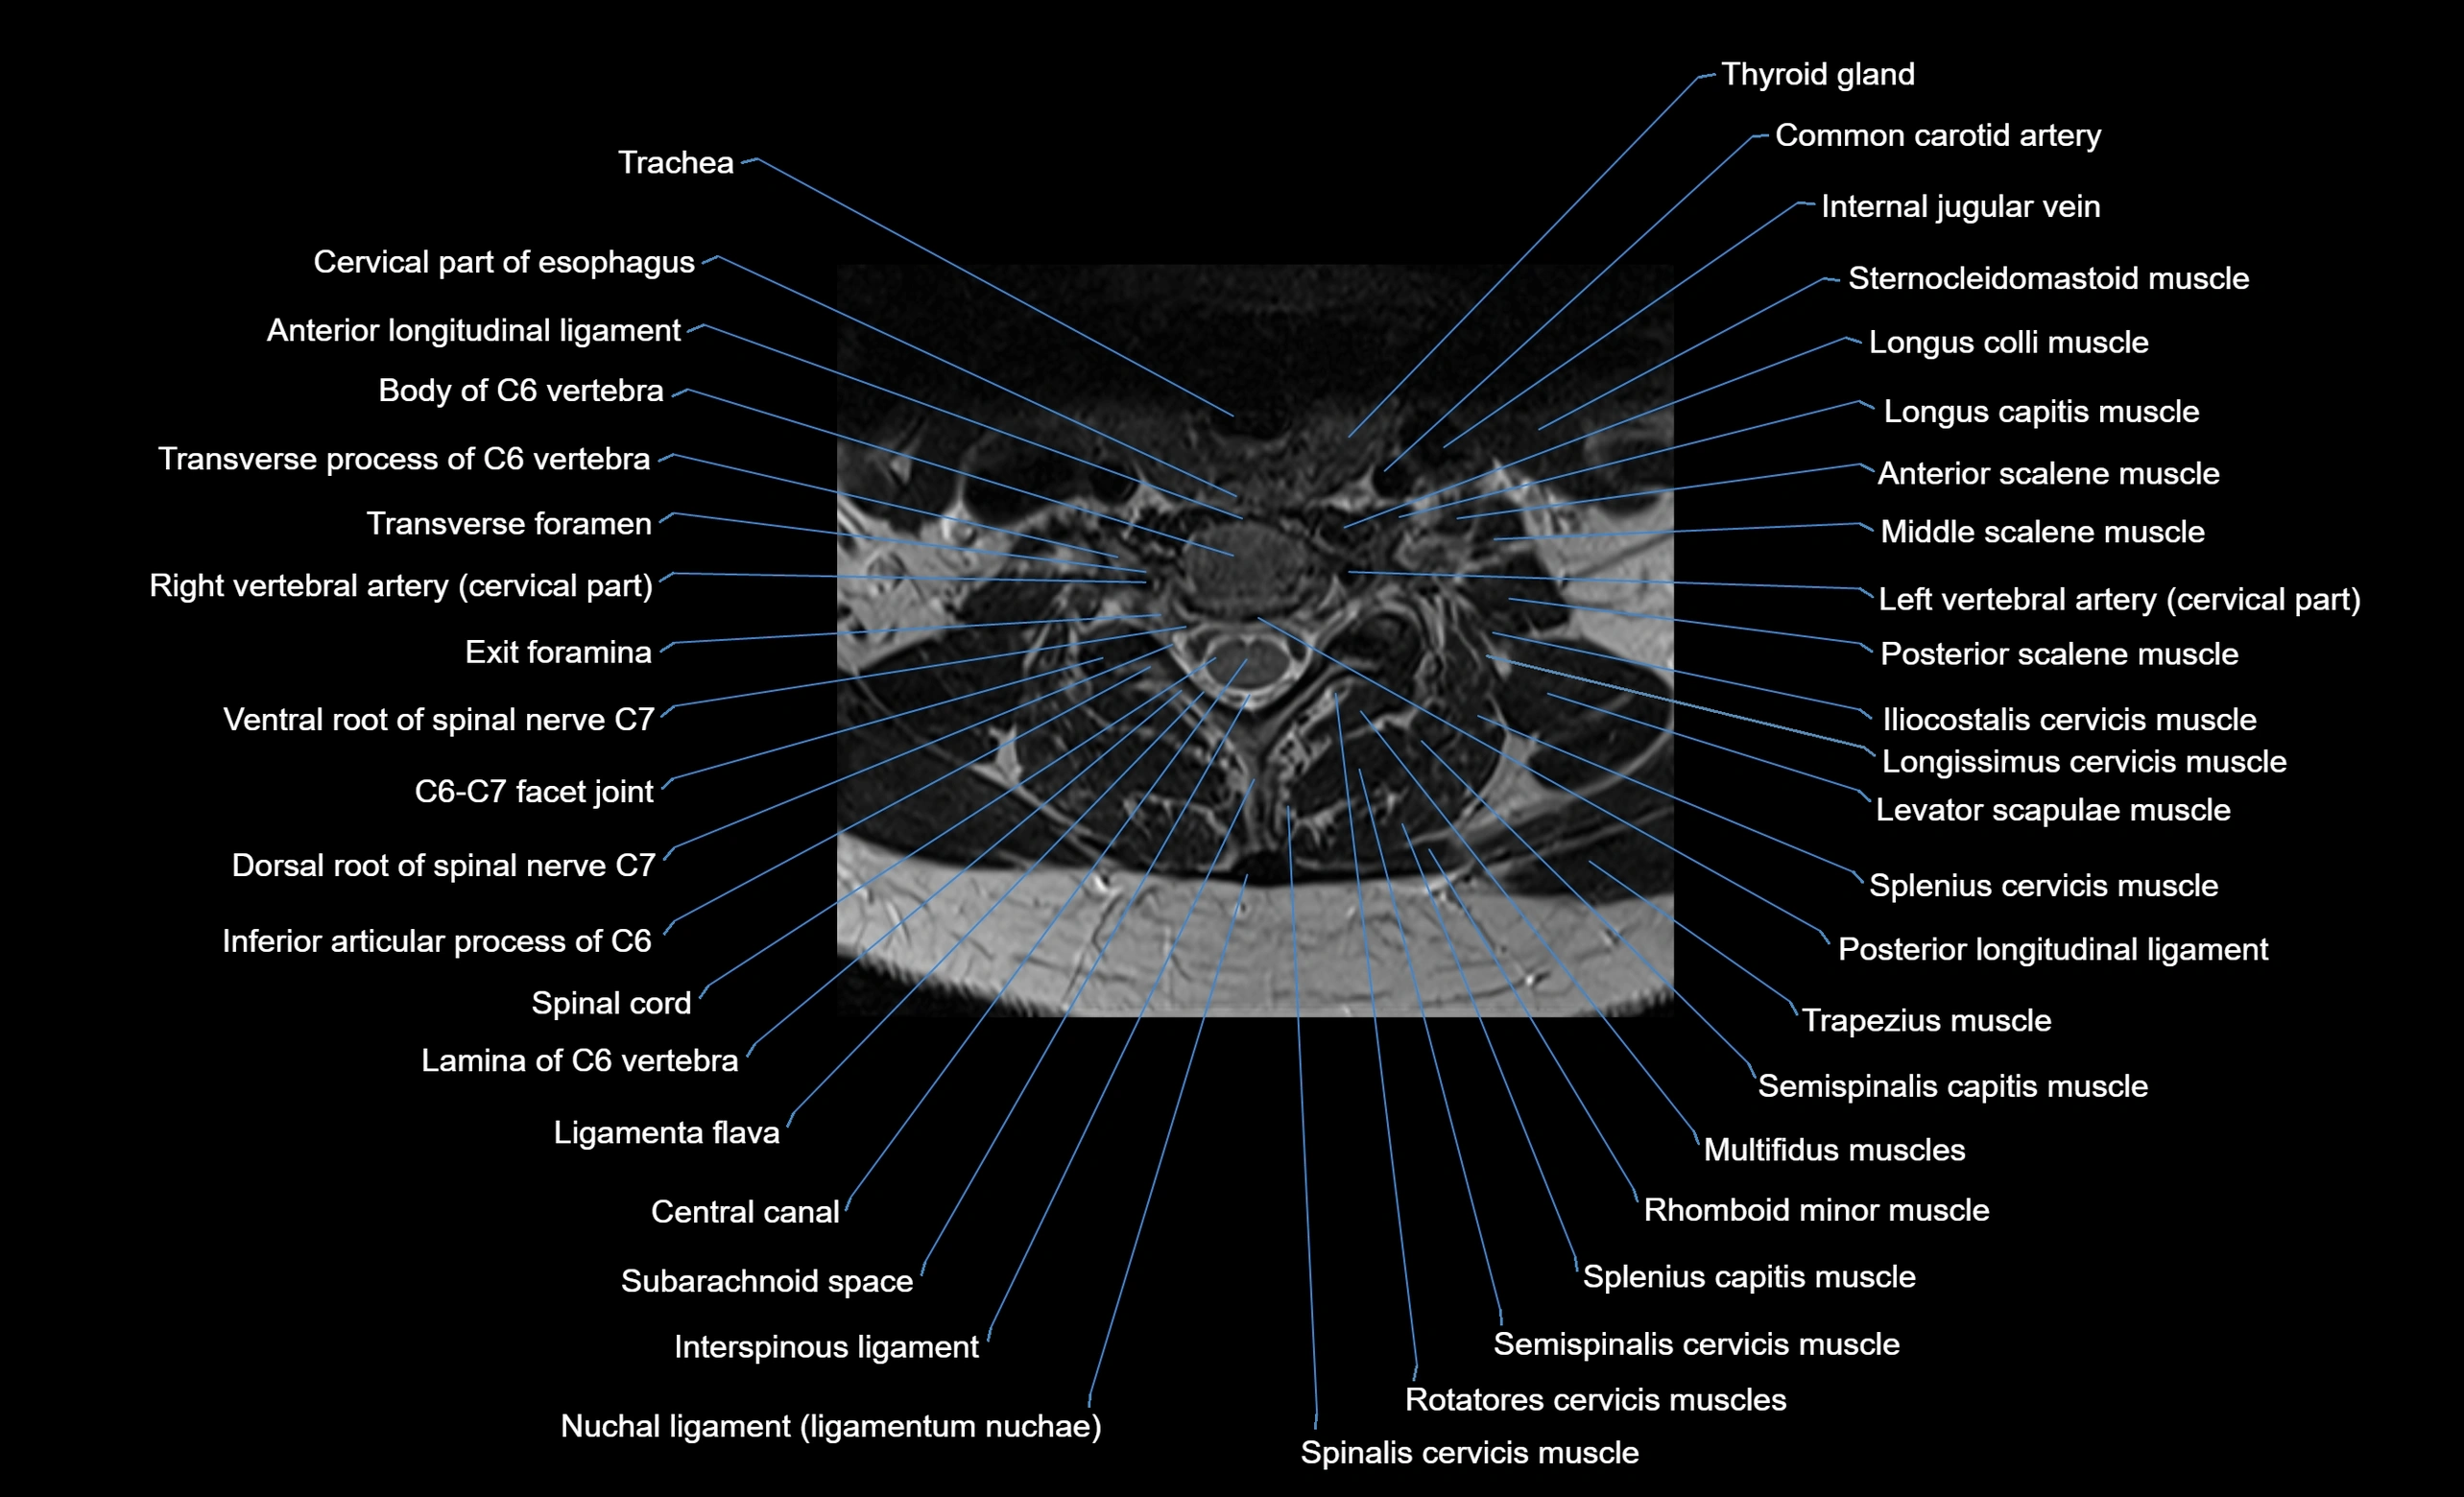

MRI image

image